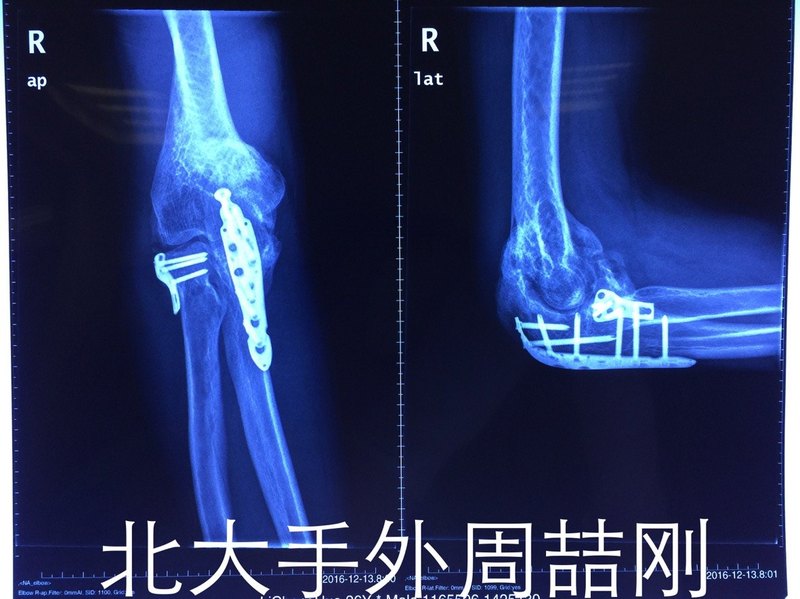

患者一年前于外院行肘部骨折內固定術 術后出現(xiàn)異位骨化及肘關節(jié)僵硬 肘關節(jié)固定于屈曲90度位 功能基本喪失 做好術前設計 根據(jù)肘部CT三維重建數(shù)據(jù) 應用國內領先3D打印模型 精確設計松解范圍,上圖示手術中3D模型應用 術后活動度明顯好轉 屈曲達100度?,伸肘達5-10度位。該病為骨科疑難雜癥,技術要求高,治療周期長,建議患者于我的專家門診就診。